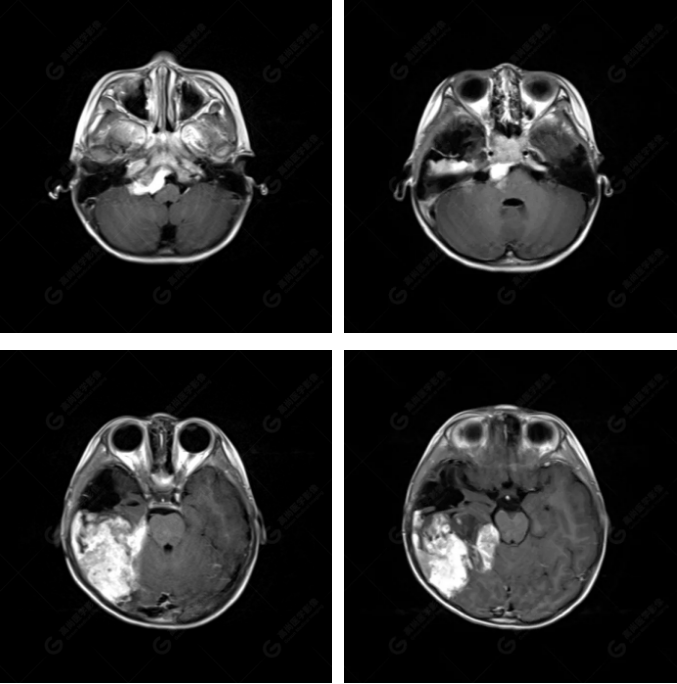

右側(cè)顳葉腫瘤切除術(shù)后(具體不詳):右側(cè)顳部骨質(zhì)不連續(xù)呈術(shù)后改變,右側(cè)顳葉術(shù)區(qū)見(jiàn)片狀長(zhǎng)T1長(zhǎng)T2信號(hào)影,F(xiàn)LAIR呈低信號(hào);術(shù)區(qū)后方右側(cè)顳枕葉見(jiàn)一巨大占位性病變影,邊界欠清,大小約6.2×5.8×4.3cm(前后×左右×上下),信號(hào)不均勻,T1WI呈等稍低信號(hào)間雜少許高信號(hào),T2WI呈高稍低混雜信號(hào),DWI示部分病灶彌散受限,相應(yīng)ADC圖減低,磁敏感序列見(jiàn)部分呈極低信號(hào),增強(qiáng)掃描可見(jiàn)明顯不均勻強(qiáng)化,鄰近硬腦膜及小腦幕增厚并明顯強(qiáng)化;另延髓右前方及右側(cè)橋小腦角區(qū)見(jiàn)一不規(guī)則形異常信號(hào)影,大小約3.2×1.3×3.7cm(左右×前后×上下),呈長(zhǎng)T1稍長(zhǎng)T2信號(hào),F(xiàn)LAIR呈等信號(hào),DWI未見(jiàn)受限,增強(qiáng)后明顯均勻強(qiáng)化,鄰近腦膜明顯強(qiáng)化。鄰近腦實(shí)質(zhì)及右側(cè)顳角明顯受壓;左側(cè)大腦半球未見(jiàn)局灶性信號(hào)異常,中線結(jié)構(gòu)稍左移。

右側(cè)顳葉腫瘤切除術(shù)后:現(xiàn)術(shù)區(qū)后方右側(cè)顳枕葉及延髓右前方占位,右側(cè)顳枕部硬腦膜及小腦幕明顯強(qiáng)化,結(jié)合既往影像資料,考慮為胚胎源性惡性腫瘤,如非典型畸胎樣/橫紋肌樣瘤(AT/RT)或原始神經(jīng)外胚層腫瘤(PNET)。